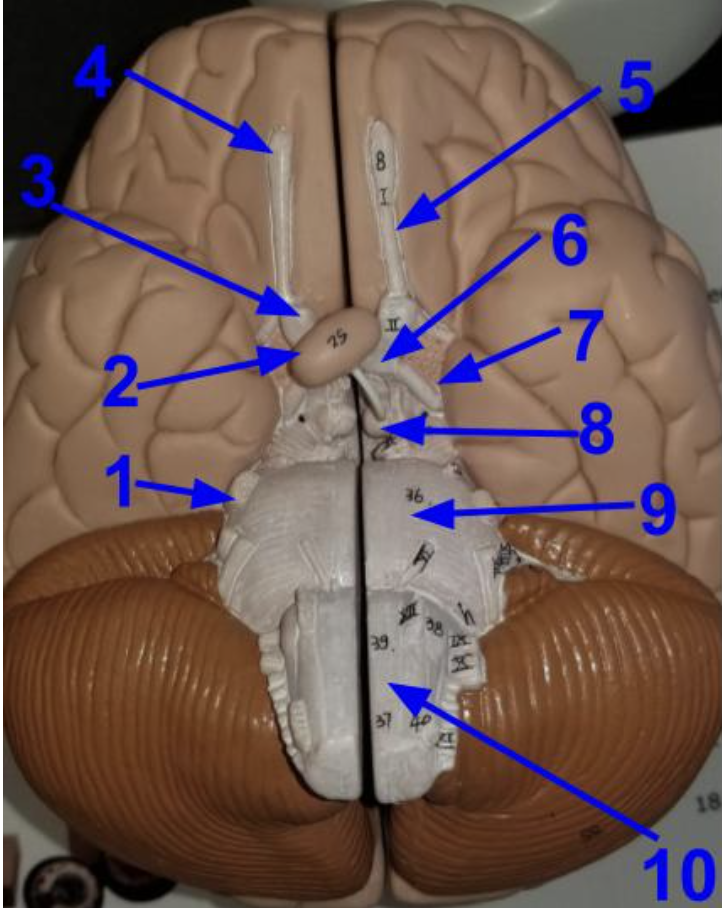

Chapter 17 - Brain Stem , Cerebellum and Cranial Nerves

what does the arrow indicate?

Olfactory bulb

What is the function of an olfactory bulb?

Receives input from olfactory neurons coming from nasal cavity

Olfactory Track

What does the olfactory tract do?

carries information from the olfactory to the cerebrum, where it can be sorted, interpreted, and processes

Optic Nerve (cranial nerve 2)

What does the optic nerve do?

carries axons from retina of the eye

what does the arrow indicate ?

Optic chiasm

What happens in the optic chiasm?

where some axons in each optic nerve cross over to the other side

What does the arrow indicate?

Optic Track

What does the optic track do?

carry axons from optic nerves ro the thalamus

What is the arrow pointing at?

Oculomotor nerve

What is the arrow indicating?

Trigeminal nerve (cranial nerve 5 /V )

What does the trigeminal nerve do?

Carries sensory information from the face

Carries motor commands to chewing muscles

Name the structures